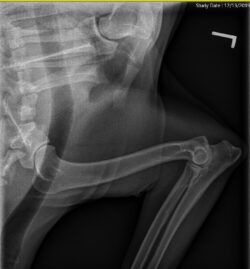

Hip clearance: OFA OFA GR-128016G24F-VPI Good